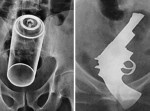

(画像)カラダの中に拳銃が! 世にも奇妙なエックス線の世界11選

カラダの中に拳銃が! 世にも奇妙なエックス線の世界11選

「カラダの中に拳銃が! 世にも奇妙なエックス線の世界11選」のページです。デイリーニュースオンラインは、